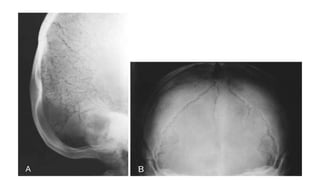

THANATOPHORIC DYSPLASIA

• Lethal dysplasia(2nd mc lethal dysplasia after osteogenesis

imperfecta type 2)

• Severely short arms and legs

• type I: marked underdevelopment of skeleton, telephone handle femurs more

pronounced

• type II

• the presence of a cloverleaf skull may be a distinctive feature

• limb shortening milder and bowing is not a feature

• proximal portions of the long limbs are

small, giving a rhizomelic appearance

• long bones (humeri and femora) have a

typical "telephone handle" bowing

with metaphyseal flaring

• Narrow chest, short ribs and scapula

• Small squared iliac wings

• Relative macrocephaly; frontal bossing

• Clower leaf skull (type 2)

• Platyspondyly